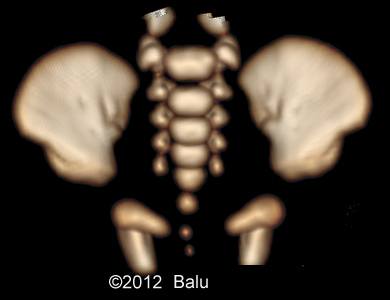

An autopsy was refused. A post-mortem X-ray and SS was performed (Image 19-24). The Apert syndrome diagnosis was confirmed by responsible mutation: p.Ser252Tp.

Images 19-24: A post-mortem X-ray and SS